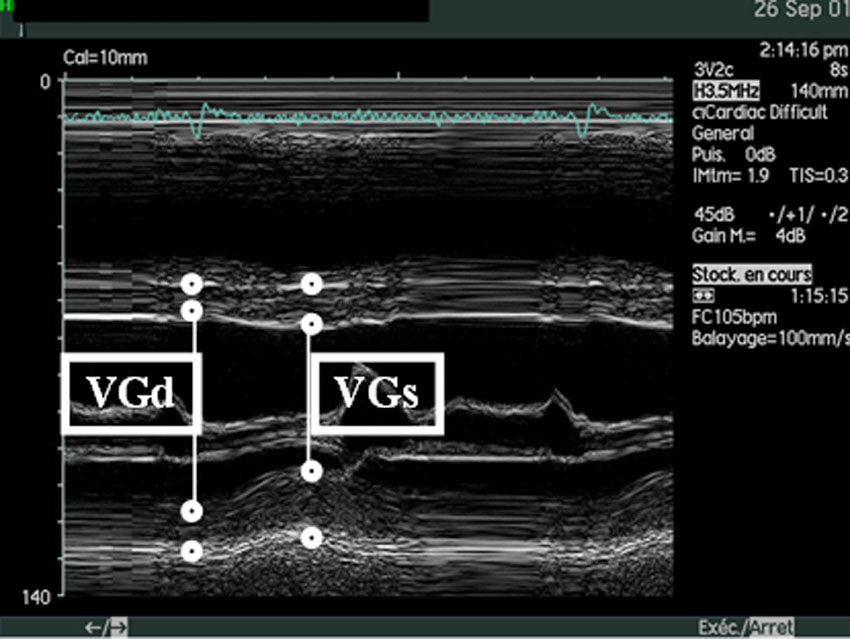

- 7 - Echocardiographie - Doppler